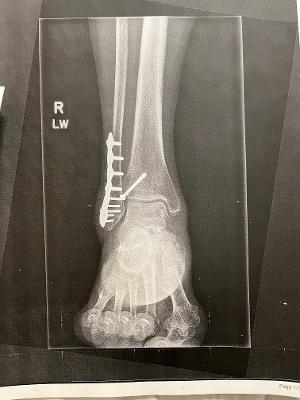

When I broke my right ankle, I thought my trip was over, but thanks to Dr. Elliott and Vinny I went to my trip within 10 months from the date of my surgery. I broke my right ankle in four parts. Dr. Elliot put it back together, and I have 10 screws and a plate (check the picture of the x-ray).